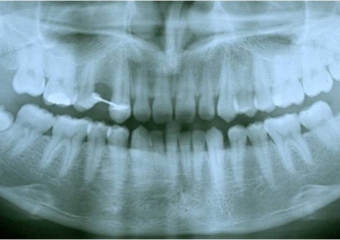

Raio X inicial